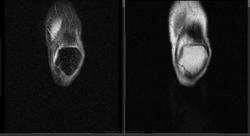

Мужчина 1963 г.р. Жалуется на боль в левом коленном суставе около 6 мес, в последний месяц стало совсем тяжко. Со слов заболел зимой, когда во время прогулки коленки сильно замерзли. Сам думаю на асептический некроз, но смущает множественность поражения.

Дмитрий, я в заболеваниях суставов не дока, но трабекулярный отек вкупе с выпотом может быть обусловлен воспалительными изменениями , но полностью начальные проявления аваскулярного некроза не могу отрицать.

я бы не поставил аваскулярный некроз. если исключена травма, дифференцировать с артритом.

Хрящ не поврежден, для артрита...